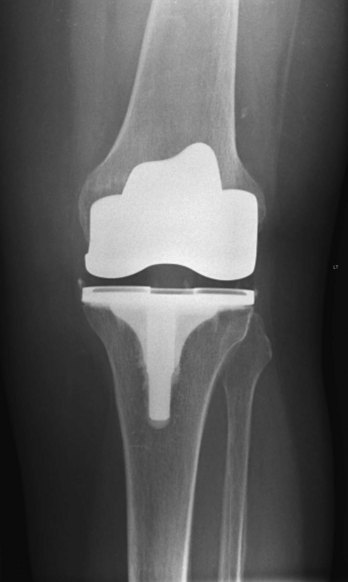

In the clinic Degenerative joint disease

Degenerative joint disease is commonly known as osteoarthritis or osteoarthrosis. The disorder is related to aging but not caused by aging. Typically there are decreases in water and proteoglycan content within the cartilage. The cartilage becomes more fragile and more susceptible to mechanical disruption. As the cartilage wears, the underlying bone becomes fissured and also thickens. Synovial fluid may be forced into small cracks that appear in the bone’s surface, which produces large cysts. Furthermore, reactive juxta-articular bony nodules are formed (osteophytes). As these processes occur, there is slight deformation, which alters the biomechanical forces through the joint. This in turn creates abnormal stresses, which further disrupt the joint (Figs. 1.23 and 1.24).

In the United States, osteoarthritis accounts for up to one-quarter of primary health care visits and is regarded as a significant problem.

The etiology of osteoarthritis is not clear; however, osteoarthritis can occur secondary to other joint diseases, such as rheumatoid arthritis and infection. Overuse of joints and abnormal strains, such as those experienced by people who play sports, often cause one to be more susceptible to chronic joint osteoarthritis.

Various treatments are available, including weight reduction, proper exercise, anti-inflammatory drug treatment, and joint replacement (Fig. 1.25).

image

Fig. 1.25 Post–knee replacement. This radiograph shows the position of the prosthesis.